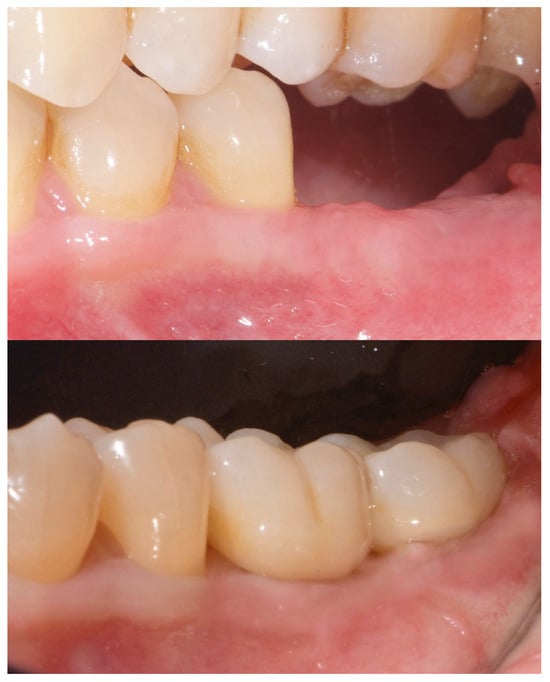

Two months later, a second-stage surgery was performed. A horizontal incision was made between the keratinized tissue and mucosa, and a partial-thickness flap was apically repositioned (Figure 9).

Figure 9. Radiographic assessment showing clear visibility of the buccal portion of the membrane left in situ.

A free gingival graft (FGG), measuring 20 mm × 6 mm, was harvested from the palatal mucosa (first premolar to first molar). The epithelial layer of the FGG was partially removed to allow for partial subflap insertion, while a portion remained exposed. The graft was stabilized with resorbable single sutures. Two months post-grafting, a screw-retained temporary restoration was placed. Four months later, two single monolithic zirconia crowns, bonded to titanium link abutments, were delivered (Figure 10).

Figure 10. Before and after prosthesis delivery. Two single monolithic zirconia crowns were delivered and bonded to titanium link abutments, ensuring functional and aesthetic rehabilitation.